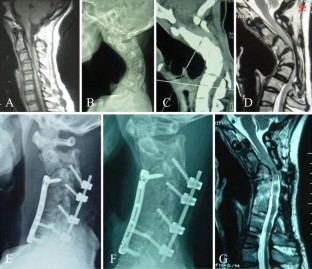

Fig. 3